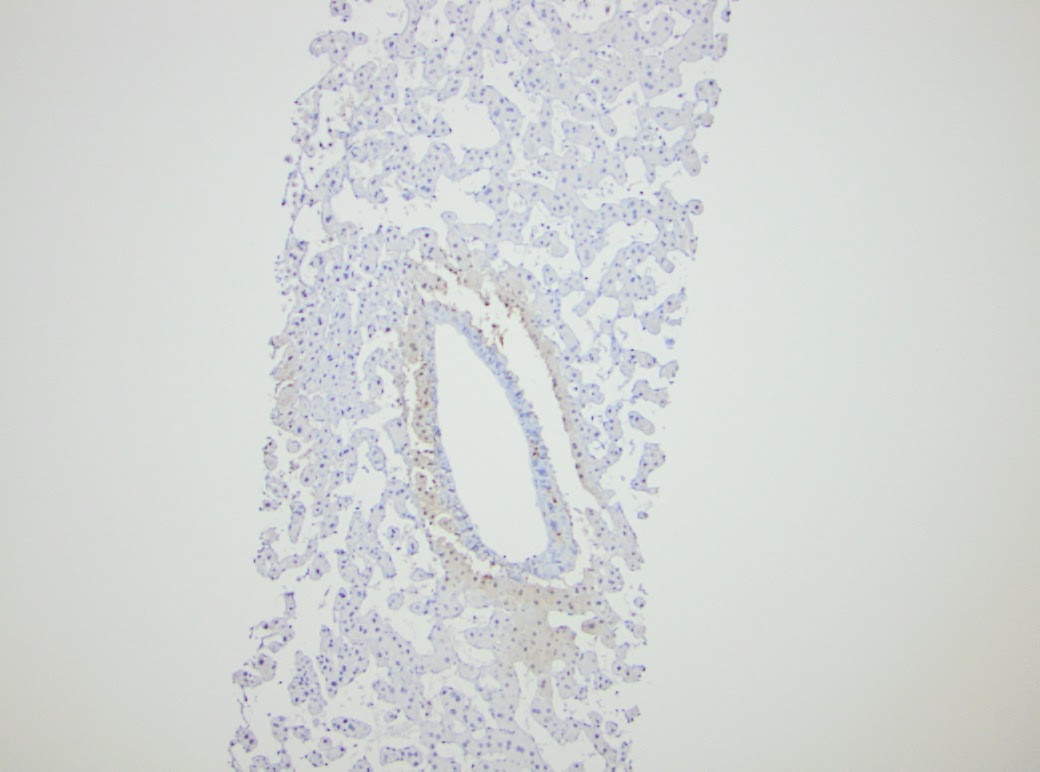

There is one vascular structure with fibrin within the lumen. No significant macrovesicular steatosis or inflammation is seen in either of the two liver biopsies. There are focal areas of hemorrhage and other areas with hepatocyte dropout. Another liver biopsy was obtained from the patient four months later in June of 2015. Again, striking zone 3 hepatocellular atrophy and sinusoidal dilatation was seen (Figure 2.) Fibrin was identified in several of the portal venules (Figure 3).

| Figure 3. June 2015 biopsy 200X |